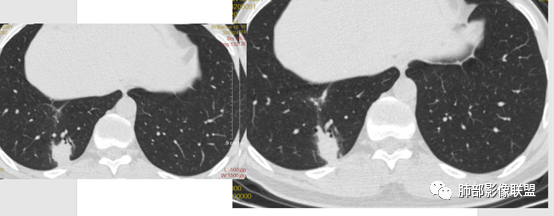

谢加平:左肺上叶和右肺下叶见多发散在性斑块病灶,边界清楚,部分见U形凹陷和刀切征,周围见模糊晕征,近胸膜下分布和蘑菇兄弟特点,累及左肺上叶上舌段支气管牵拉性扩张,前后13天复查整体病灶吸收不明显,有机化趋势表现,首选炎性肉芽肿(隐球菌感染?),请结合隐球菌荚膜抗原检查。

小兜:男性,39岁,3周前劳累受凉史,次日至三亚开始咳嗽咳痰,入院时自述症状减轻。CT示双肺多发斑片影,部分病灶内部支气管壁增厚扩张穿行,平扫密度均匀,增强未见明显坏死,治疗前后部分病灶略吸收。实验室检查白细胞血沉轻度增高。考虑隐球菌感染可能,鉴别类鼻疽,淋巴瘤。

傅昌瑜:青年男性,咳嗽咳痰3周。白细胞计数稍升高,CRP正常。两肺多发斑片状、结节影,周围见边缘模糊磨玻璃影,部分边缘见毛刺,支气管穿行稍扩张。治疗后(具体药物不详),周围磨玻璃影减少,病灶似乎变小。无明显发热、白细胞无明显升高、CRP正常,治疗10天后复查吸收不明显,不支持细菌性肺炎。无发热、鼻窦疾病及血尿(未提供相关检查)等,血管炎可能性不大。肺内病灶形态单一类似、无树芽征,不支持肺结核。综合考虑隐球菌可能性大,鉴别淋巴瘤、血管炎。

* 差不多2周,有差异吗?半个月左右吸收明显,肿瘤不考虑,炎性没问题。

* 看看这边缘,平直、凹陷,炎性没问题,修复阶段。提示亚急性,有OP形成;多发,斑片,强化偏轻,常规抗炎效果不佳。首先:诊断炎性病变,三亚,多发病灶,斑块状,周围GGO,类鼻疽要考虑。

2、影像资料:双肺多发的小结节、斑片状及不规则型的实性病灶,周围有晕,沿支气管血管束分布,部分的病灶周围可见磨玻璃样影、支气管的扩张以及小的空洞。增强扫描病灶,轻度强化内部见支气管造影征。部分的病灶,支气管有扩张,内壁凹凸不平的改变,纵隔淋巴结未见肿大。病灶整体的形态还是多样化,部分位于胸膜下。

3、治疗:经氟康唑治疗2周后,影像上以边缘的磨玻璃样病灶的吸收为主。